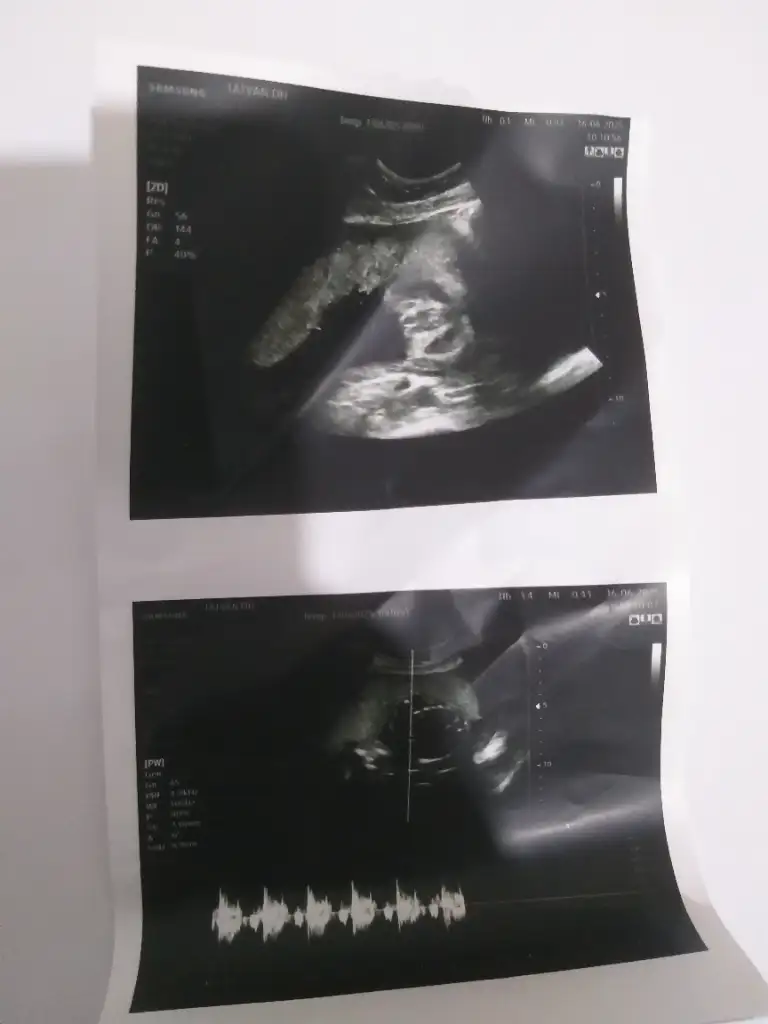

Rica etsem bana da tahminde bulunur musunuz? 25 haftalığız hiç sormadım doktorumuzdan😂😊😊😊